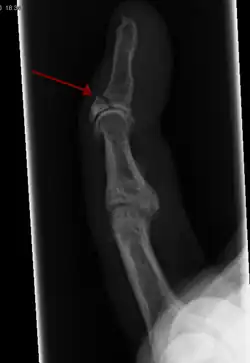

- Broken finger – a fracture of the carpal phalanges